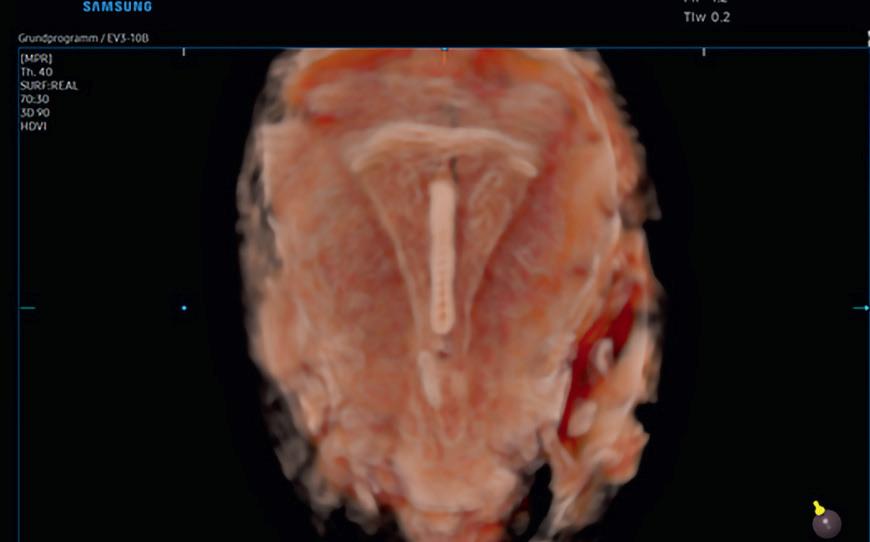

Våre erfaringer med hjemmeinduksjonsstudien er at dette bør være et alternativ til kvinnene som induseres, og vi har tatt metoden inn i vår lokale induksjonsprosedyre. Hos oss har vi gjort enkelte endringer etter studien, blant annet kan kvinner med vannavgang også få misoprostol hjemme. Ellers har vi økt til maks 8 tabletter i 2 påfølgende dager, men kvinnene kommer inn til sykehuset neste dag for å hente resterende 8 tabletter. På denne måten sparer vi tabletter som ikke blir brukt, og ikke minst får vi en kontakt med kvinnene slik at de lettere kan gi beskjed om problemer, spørsmål eller annet. Vi tar kun CTG før 1. dose misoprostol. Kvinnene som egner seg informeres om at de kan være hjemme, istedenfor at de informeres om at det er en mulighet å være hjemme. Alle får skriftlig informasjon om hvordan de skal ta tablettene hjemme og når de skal henvende seg til avdelingen. Flyten og den praktiske gjennomføringen av induksjonsstrømmen er vi således allerede i gang med å optimalisere.

Inntrykket vårt er at det å være hjemme i starten av induksjonen gi mer ro, komfort og trygghet totalt enn det vi kan tilby ved innleggelse, spesielt for flergangsfødende. Vi tror også at tabletter fremfor ballong kan være en enkel, skånsom og praktisk måte å bli indusert på, som både vi og kvinnene det gjelder vil trives med. Vi kommer gjerne tilbake med tall og resultater.

Fortsettelse følger!

25 Medlemsblad for Norsk Gynekologisk Forening

Kikhostevaksine

Gravide blir en målgruppe i barnevaksinasjonsprogrammet